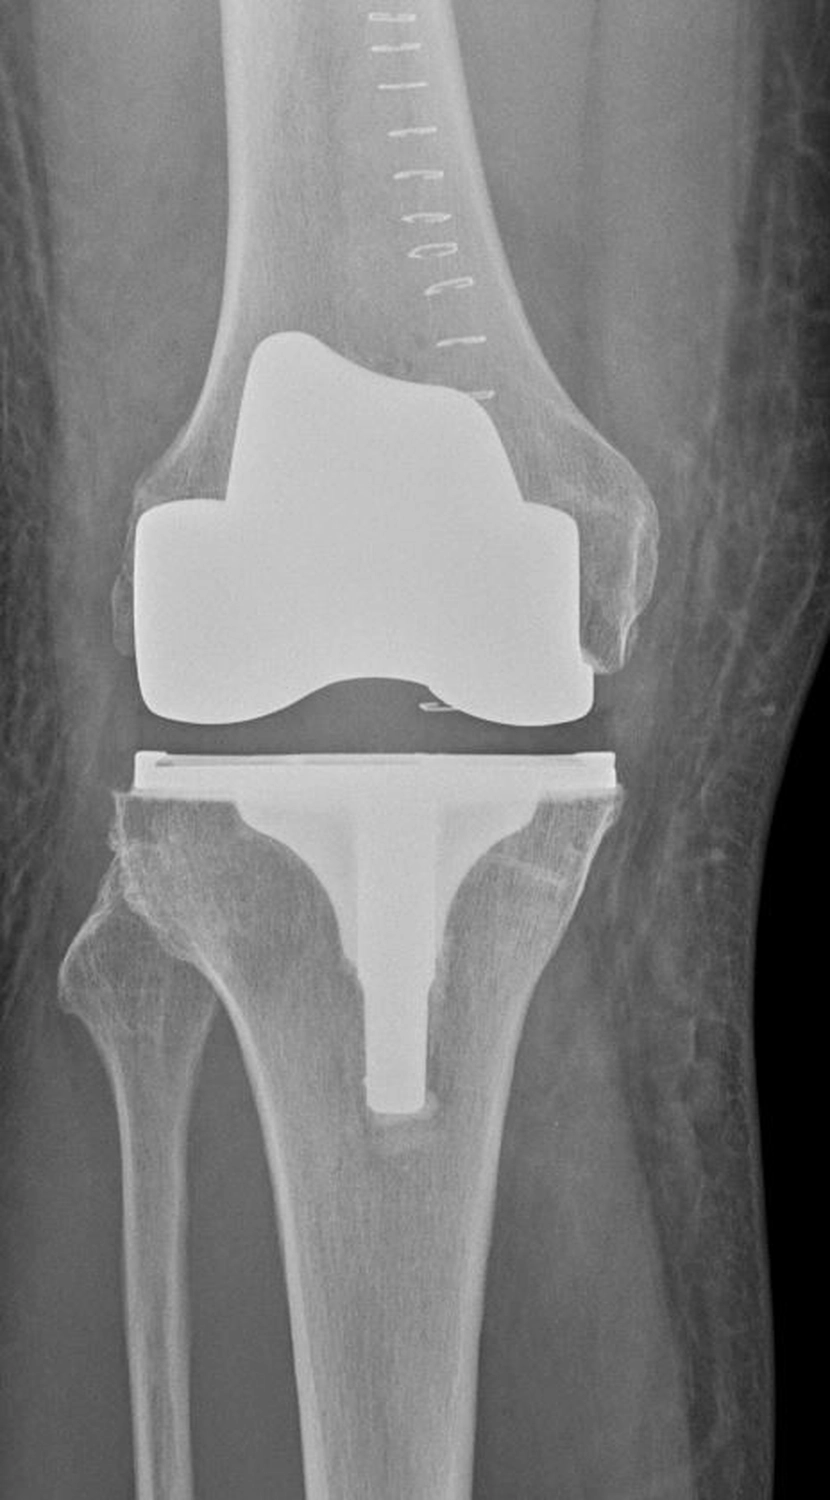

Bei der Implantation einer Knieprothese werden die zerstörten Gelenkflächen des Oberschenkel- und Schienbeinknochens millimetergenau entfernt und durch passgenaue Metallkomponenten ersetzt.

Dazwischen liegt ein hochbelastbares Kunststoffinlay, das die Gleitfläche bildet.

Bei der Implantation einer Knieprothese werden die zerstörten Gelenkflächen des Oberschenkel- und Schienbeinknochens millimetergenau entfernt und durch passgenaue Metallkomponenten ersetzt. Dazwischen liegt ein hochbelastbares Kunststoffinlay, dass die Gleitfläche bildet.